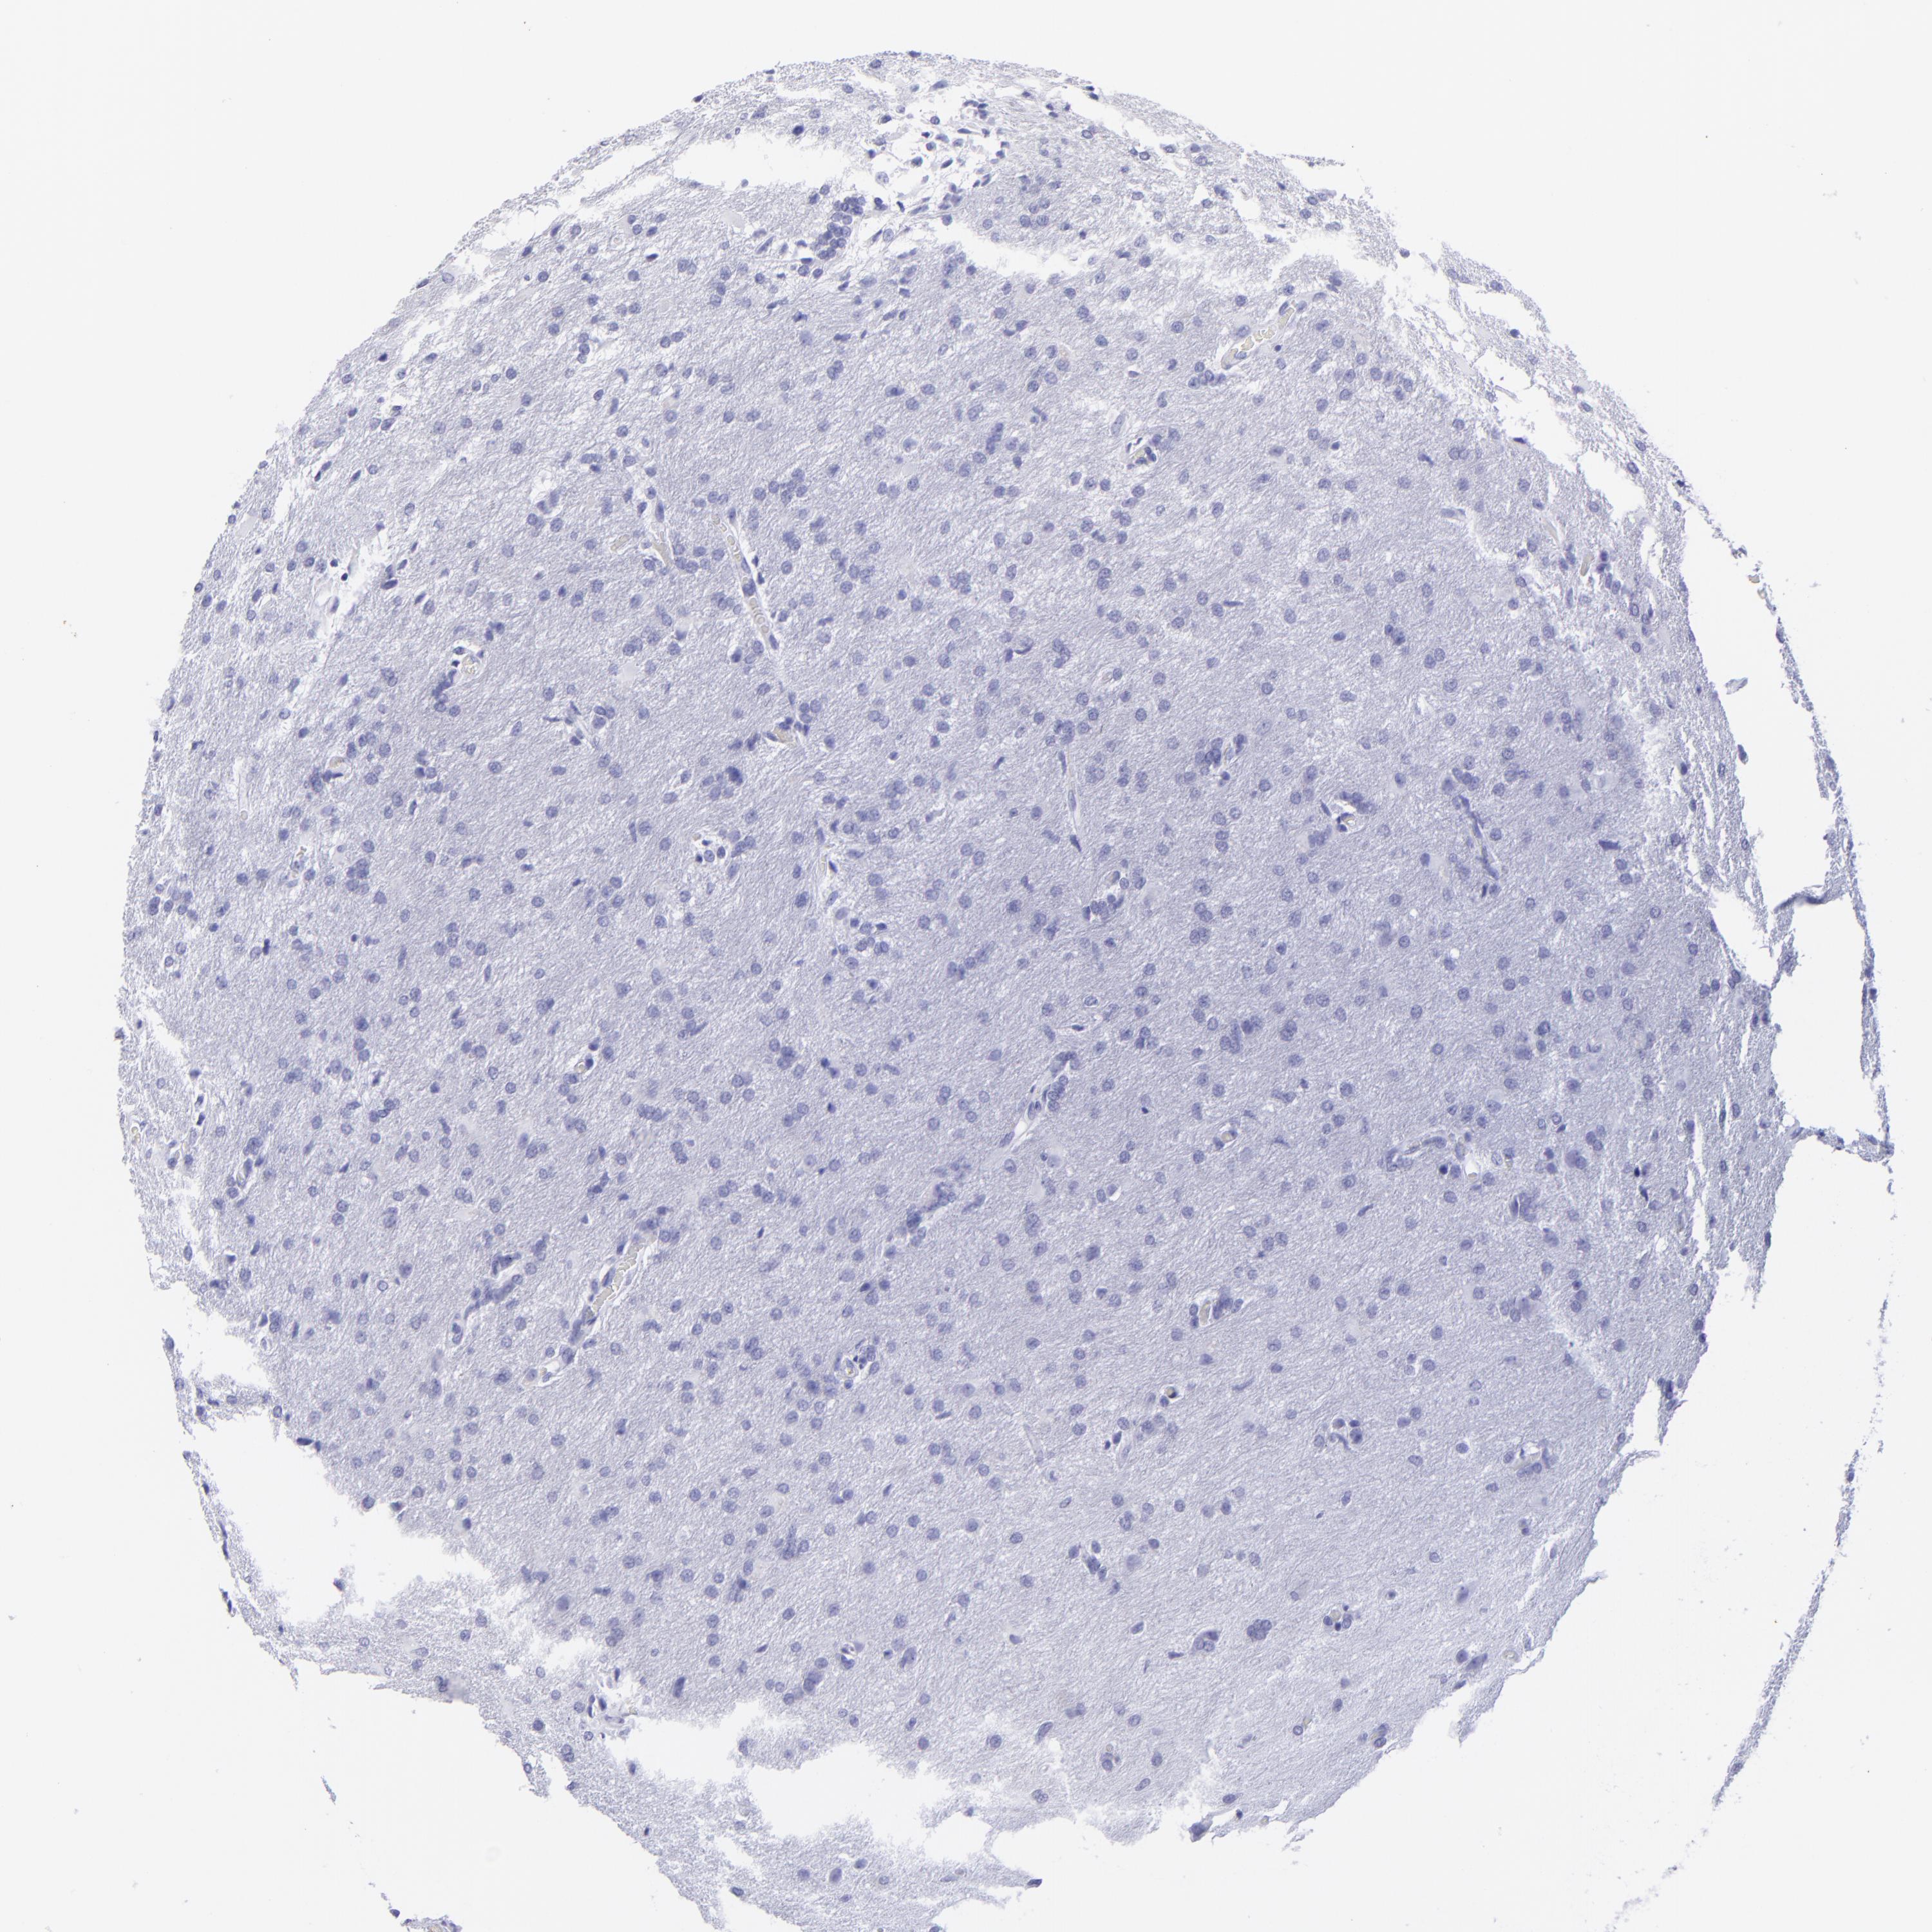

GLIOMA - Protein expressioni

A mouse-over function shows sample information and annotation data. Click on an image to view it in a full screen mode. Samples can be filtered based on level of antibody staining by selecting one or several of the following categories: high, medium, low and not detected. The assay and annotation is described here.

Antibody stainingi

Antibody staining in the annotated cell types in the current human tissue is reported as not detected, low, medium, or high, based on conventional immunohistochemistry profiling in selected tissues. This score is based on the combination of the staining intensity and fraction of stained cells.

Each image is clickable and will lead to virtual microscopy that enables deeper exploration of all samples and also displays staining intensity scores, fraction scores and subcellular localization as well as patient and tissue information for each sample.

Antibody HPA009177

Antibody CAB002661

Staining

Not detected

Intensity

Negative

Quantity

None

Location

Glioma, malignant, High grade

Glioma, malignant, Low grade